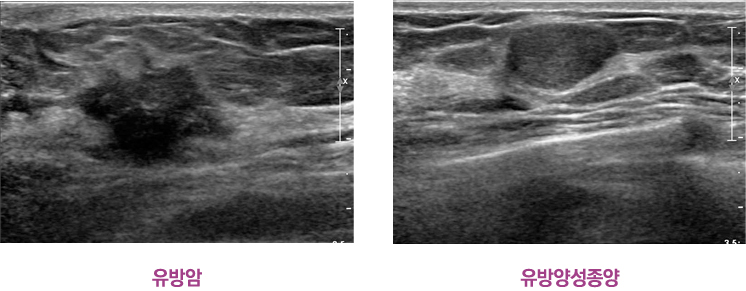

°íÇØ»óµµ ÃÊÀ½ÆÄ ±â±â¸¦ ÀÌ¿ëÇÑ °Ë»ç

´ÜÃþ ¿µ»óÀ¸·Î Á¤»ó°ú ÀÌ»ó ±¸Á¶¹°ÀÇ ±¸º° °¡´É

§® ´ÜÀ§ÀÇ ¹Ì¼¼ÇÑ Á¾±«µµ ¹ß°ß °¡´É